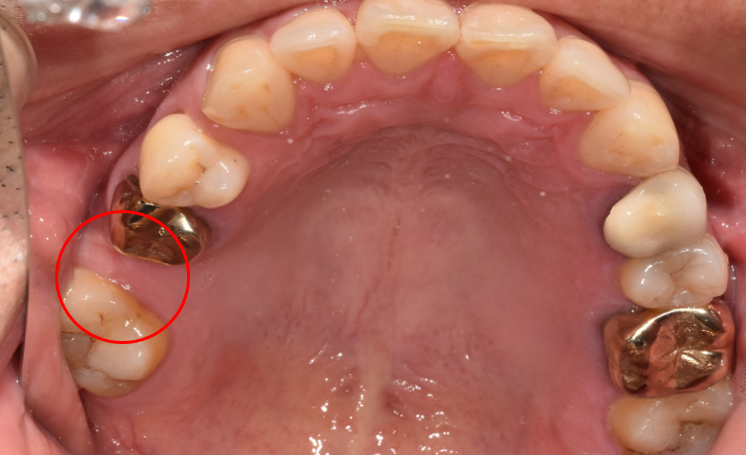

청담역치과 2021-11-01

4단계는 자연치아와 흡사하게 본을 떠서 만든 인공치아를 장착해 치료를 완료했습니다.

청담역치과 2021-11-01 치아 중앙에 구멍, 보이시나요?

치료 후 사진을 자세히 보시면 사진 중에서 구멍이 살짝 보이실 것입니다.

그것이 바로 위에 설명드렸던 'SCRP 타입'의 보철물인데요.